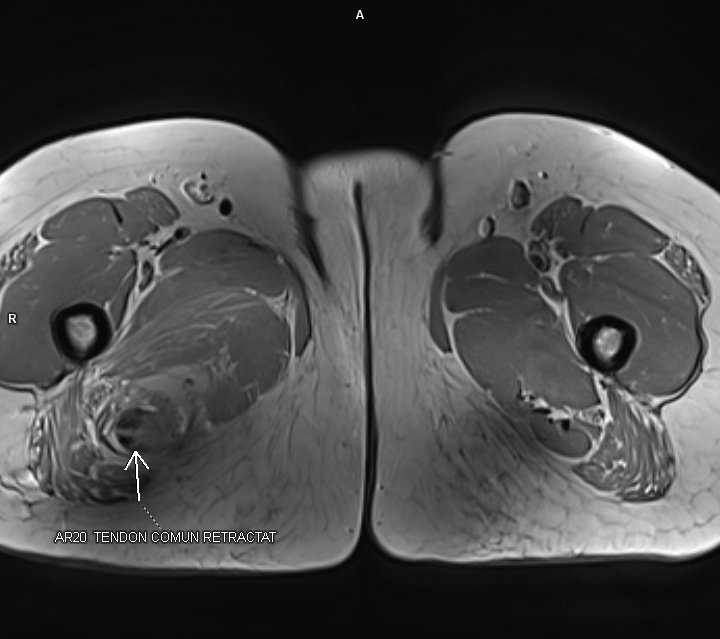

Figurile 5, 6 si 7: axial T1 coapsă bilateral

Discuţie caz nr 92: Harmstring lesion este dificil de tradus în limba română și se referă la leziunea celor trei mușchi ce se inseră pe tuberozitatea ischiadică: semitendinos, semimebranos și biceps femural. Cazul prezentat este a unui pacient care s-a aplecat la cumpărături să ridice o plasa și a simțit o durere puternică în spatele coapsei urmată de impotența funcțională si de creștere de volum a coapsei posterior. Pe imaginile postate se evidențiază avulsia tendonului comun al celor trei muschi ce se regăsește retractat inferior cu formarea unui hematom în vecinătate.